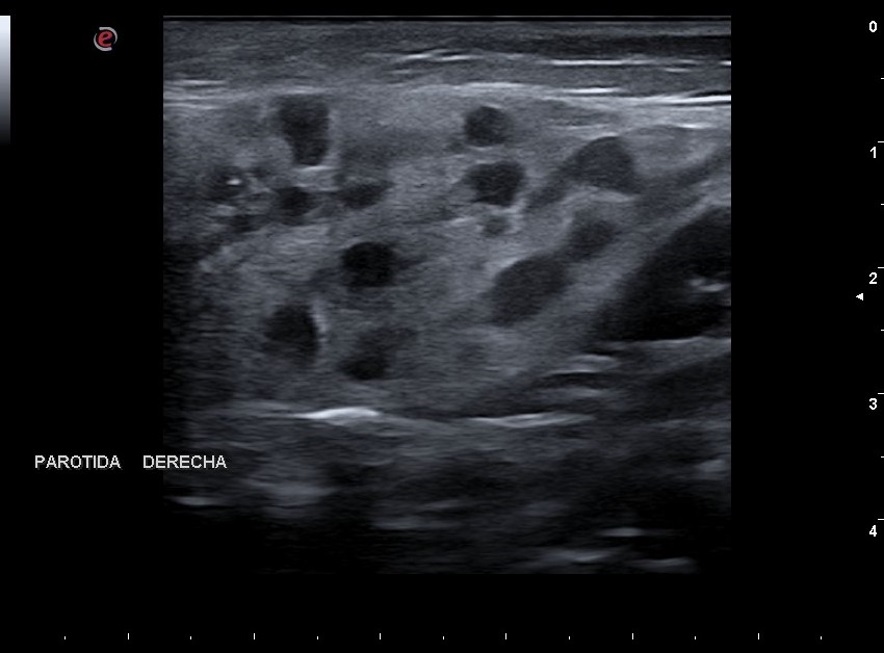

Varón de siete años que acude por una tumefacción dolorosa temporomandibular derecha, sin otra sintomatología. En la exploración se constata una tumefacción parotídea derecha, sin obstrucción del conducto de Stenon. Correctamente vacunado. Antecedente de convulsiones febriles y obesidad. Se realizó una ecografía donde se visualizaron lesiones quísticas en la región parotídea derecha de 1 cm de diámetro, numerosas adenopatías regionales de aspecto ovalado, borde bien delimitado y vascularización central (Fig. 1). En la analítica, el hemograma resultó normal, con leve linfopenia. Serología: parotiditis IgG+, IgM, negativa para virus de la inmunodeficiencia humana. Ante la sospecha de parotiditis crónica, se realizó tratamiento sintomático con analgesia pautada, con mejoría clínica del dolor y de la tumefacción a los 3 días de tratamiento.

Figura 1. Ecografía parotídea derecha. Múltiples imágenes quísticas con adenopatías regionales